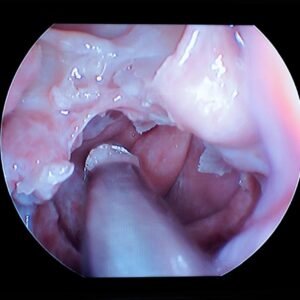

Anatomia cirúrgica e radiológica dos seios paranasais

Sinusotomias Maxilar, Etmoidal, Esfenoidal, Frontal

O Curso Endobrasília chega à sua terceira edição, consolidado como uma das principais imersões em cirurgia endoscópica nasal do país. Sempre muito bem avaliado pelos alunos, destaca-se pela combinação de conteúdo teórico de excelência, professores altamente dedicados e treinamento prático personalizado, proporcionando uma experiência completa e transformadora para otorrinolaringologistas e residentes.

No módulo teórico, os participantes terão acesso a aulas ministradas por especialistas reconhecidos, abordando técnicas cirúrgicas atualizadas, dicas fundamentais e estratégias para identificação segura dos reparos anatômicos essenciais. Essa base sólida prepara o aluno para executar as intervenções com segurança, precisão e maior confiança.

O treinamento prático, realizado em peças anatômicas frescas, oferece um ambiente realista para aquisição e refinamento de habilidades na dissecção endoscópica nasal. Cada estação é equipada com videoendoscopia de última geração, motores de alta performance e instrumentais cirúrgicos modernos, garantindo um hands-on de altíssimo nível, sempre sob acompanhamento próximo de cirurgiões experientes.